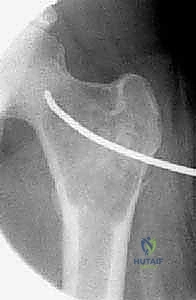

تُظهر هذه الأشعة السينية (X-ray) كيس عظم أحادي الغرفة (UBC) في الجزء العلوي من عظم العضد. لاحظ كيف أن الكيس يسبب ترققاً في قشرة العظم دون أن يخترقها.

- في الـ UBC، تظهر الآفة كمنطقة شفافة (سوداء) مركزية داخل العظم. وهناك علامة مميزة تُسمى "علامة الورقة المتساقطة" (Fallen Leaf Sign)، حيث تسقط قطعة صغيرة من قشرة العظم المكسورة داخل الكيس المملوء بالسائل، وهي علامة مؤكدة بنسبة 100% تقريباً على الـ UBC.